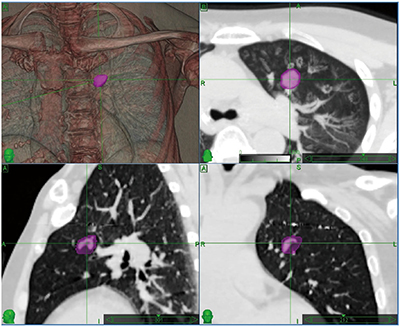

図5 Time-MIP画像

上段右のaxial像がTime-MIP画像、紫色で囲まれた領域がITVである。下段のsagital、coronal像は呼気停止にて撮影したCT画像である。